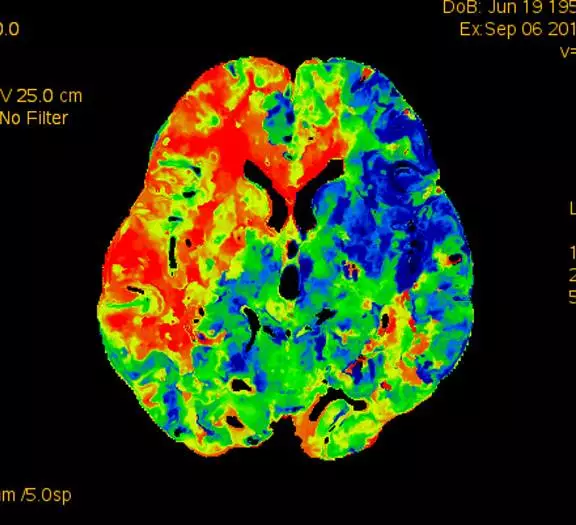

术前CTP示:右侧大脑半球灌注较差。

术后2个月患者未再诉右眼黑曚。复查CTP示:颅内灌注明显改善。